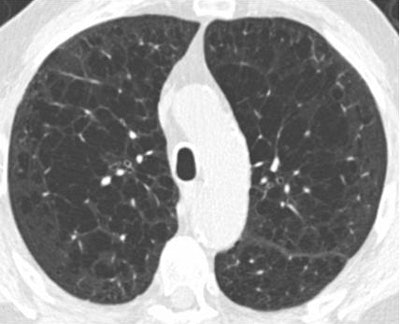

Above, patient with centrilobular emphysema; below, patient with paraseptal emphysema. Both COPD phenotypes were associated with malignancy in nodules 6 mm to 19 mm in diameter at CT lung cancer screening. Images courtesy of Dr. David Gierada and Dr. Caroline Chiles.

Above, patient with centrilobular emphysema; below, patient with paraseptal emphysema. Both COPD phenotypes were associated with malignancy in nodules 6 mm to 19 mm in diameter at CT lung cancer screening. Images courtesy of Dr. David Gierada and Dr. Caroline Chiles.Factors not associated with emphysema were bronchial wall thickening at any level of severity (odds ratio, 0.92), centrilobular nodularity (odds ratio, 1.05), and pulmonary fibrosis (odds ratio, 1.05).